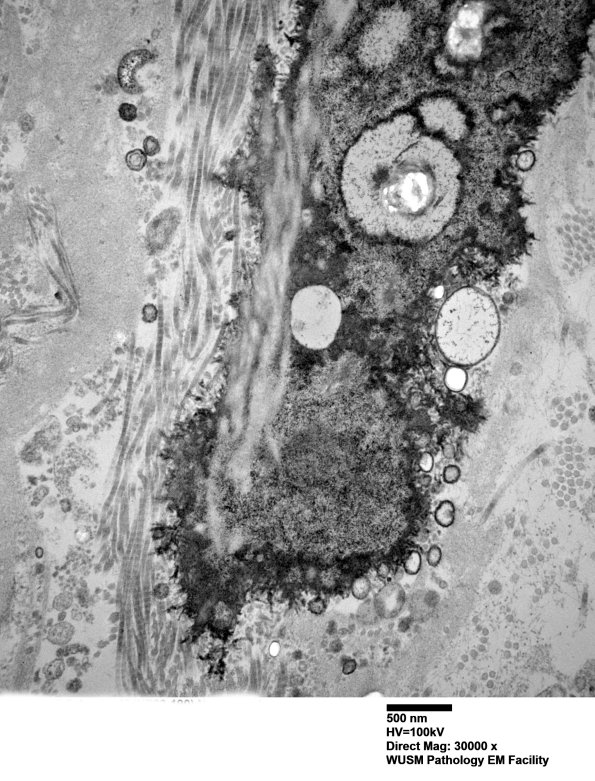

Additional images of perineurial calcification. Perineurial calcifications can be seen in normal individuals as a function of age and as a nonspecific feature of peripheral neuropathies. (electron micrographs) ---- Not shown: The majority of structures reminiscent of onion bulbs in plastic sections have a different appearance in which processes devoid of axons cluster together, a pattern of pseudo-onion bulb formation which is not a demyelinative pattern